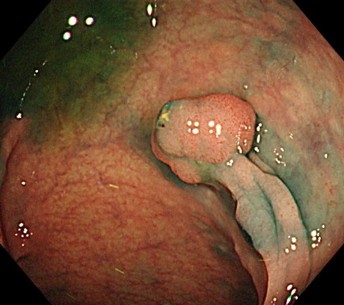

ある患者さんが、健康診断で胃カメラ(上部内視鏡)を受けたところ、食道に白っぽいポツポツとした盛り上がりが見つかりました。これは「グリコーゲンアカントーシス」と呼ばれるもので、基本的には良性の変化です。でも、もしこの変化が目立ってたくさん見られる場合、実は「大腸がん」や「甲状腺がん」、「乳がん」などになりやすい体質が隠れていることがあるんです。

そこで私たちは、そのことを患者さんにしっかり説明し、苦痛をできるだけ少なくするために鎮静剤を使いながら、大腸カメラを定期的に受けていただくことにしました。すると、なんと!とても早い段階(ステージ0)の大腸がんを見つけることができ、無事に早期治療まで進めることができました。